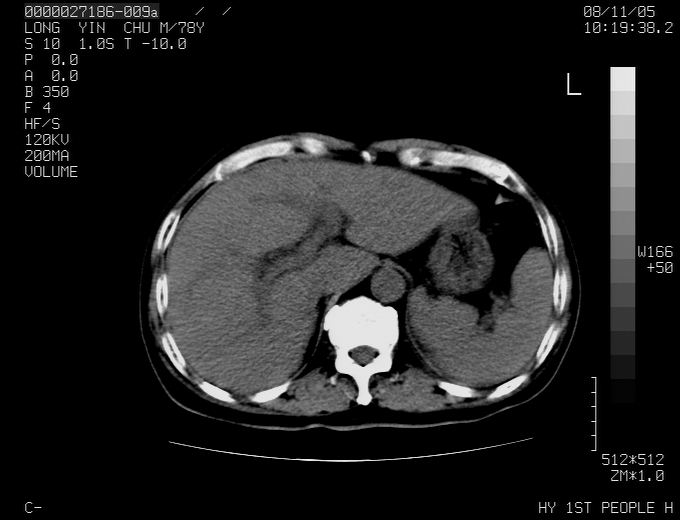

标题: CT16532:M78Y,肝脏病变,请会诊 [打印本页]

标题: CT16532:M78Y,肝脏病变,请会诊

腹胀,腹痛就诊,男性,78岁,外院b超未见异常。

肝ca,脾肾转移

考虑弥漫性肝癌并脾及双肾转移.双侧胸水.

图片质量欠佳:多考虑:左侧肾癌。脾脏转移!胸膜转移!

肝脾肾转移瘤可能性大,左肾不除外梗塞,双侧胸水

考虑弥漫性肝癌并脾及双肾转移,双侧胸水。

考虑肝癌并双肾及脾脏转移;双侧胸腔积液。